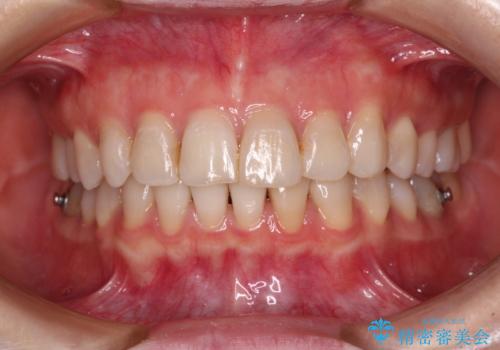

前歯の突出感とデコボコをインビザライン矯正で改善

- 上下前歯の突出感とデコボコを気にして来院された患者様です。

インビザラインによる上下歯列の側方拡大と後方移動、IPR(歯と歯の間を削る)にるスペースの獲得により歯列を整えることとしました。

骨格的な左右差があったため、上下の正中を合わせることができませんでした。

骨格の差は改善できないため、奥歯の咬み合わせに物足りなさを感じましたが、奥歯の咬み合わせによる不自由はなく、口元の突出感も改善することができました。